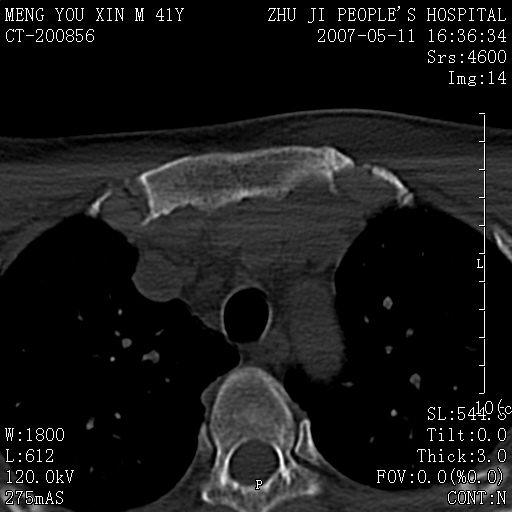

标题: CT8190:左锁骨胸骨端骨病,请会诊.

一周前左肩部酸痛,三天前颈部扭伤,后颈部摄片示颈椎病.现胸锁关节处肿痛明显.无发热.自诉三年前车祸安全气囊弹出.

左侧锁骨近端膨大,骨皮质中断,并见少许骨膜反应,内见破坏,边缘见筛孔征,无硬化.因此考虑骨巨细胞瘤可能.

1,不支持结核,此例胸壁肿胀不明显,锁骨后方是局限性肿物而非脓肿,考虑为恶性肿瘤2,左侧锁骨近端膨大,骨皮质中断,并见少许骨膜反应,内见破坏,边缘见筛孔征,无硬化.因此考虑骨巨细胞瘤可能.